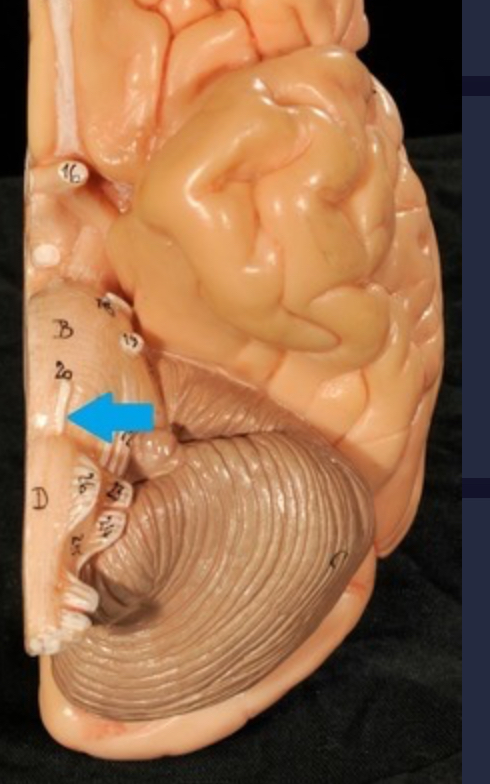

Brain stem

Pons

Medulla oblongata

I. Olfactory

II. Optic

III. Oculomotor

IV. Trochlear

V. Trigeminal

VI. Abducens

VII. Facial

VIII. Vestibulocochlear

IX. Glossopharyngeal

X. Vagus

XI. Accessory

XII. Hypoglossal